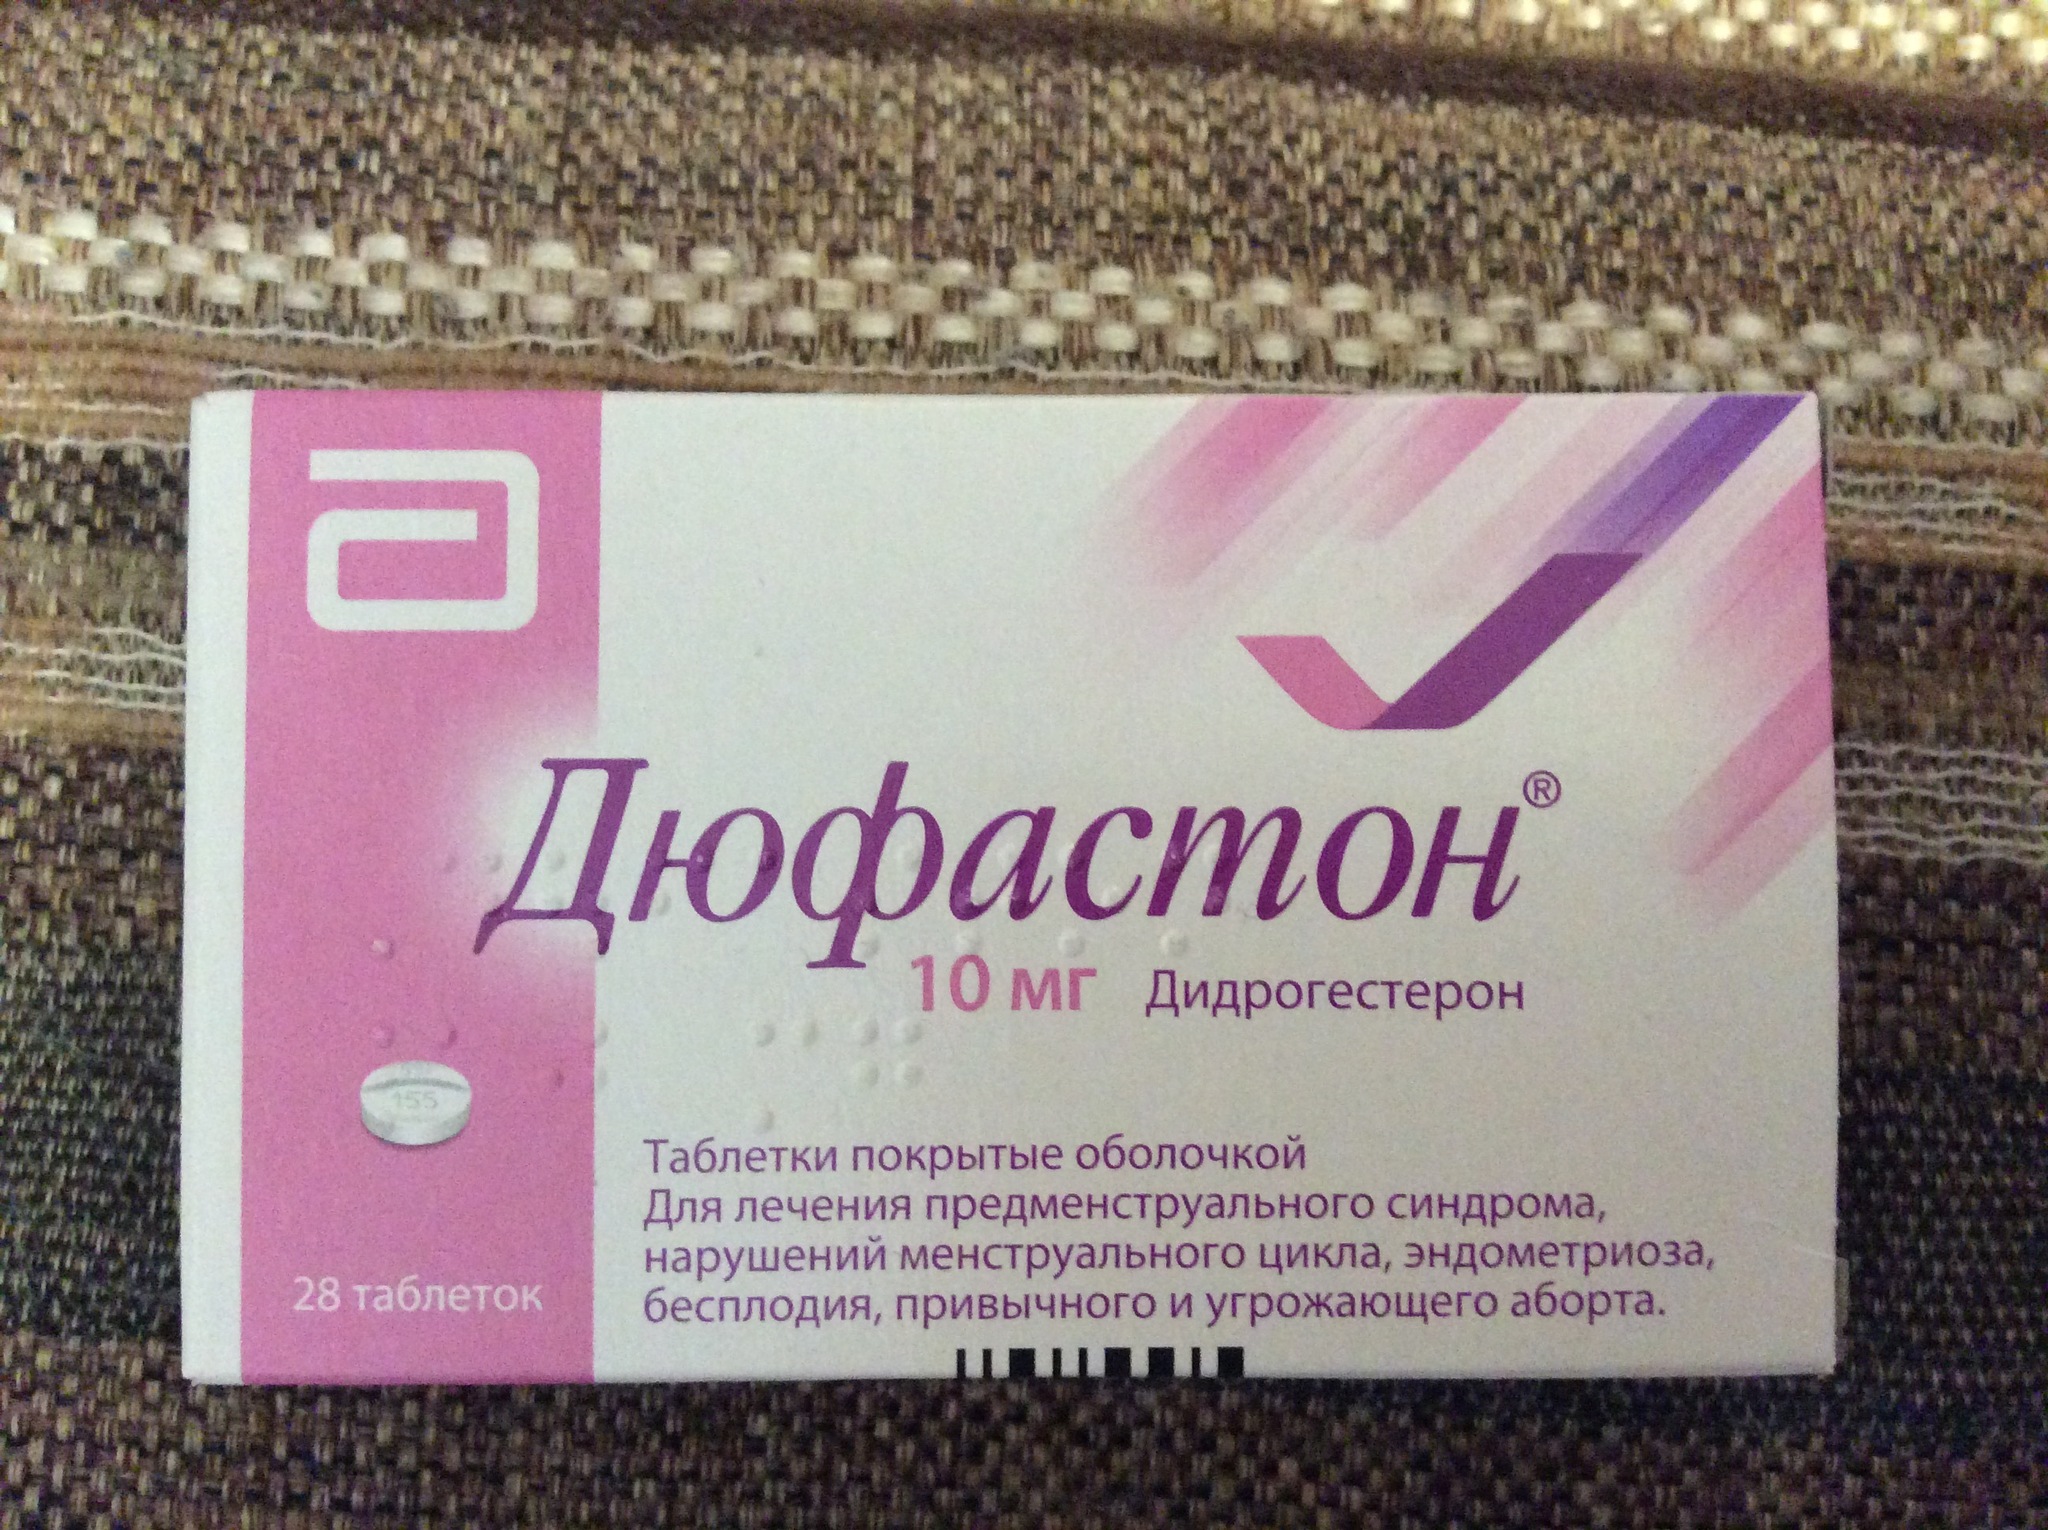

Рекомендации по зачатии